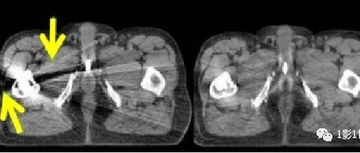

这样的图像咋诊断 | CT伪影

#屏气发作

2026.03.22

543浏览